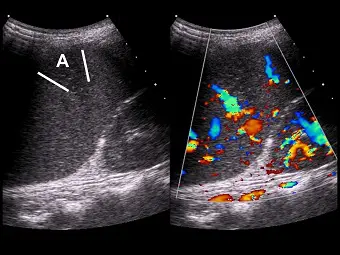

超音波掃描一位肝硬化併有門脈高壓患者,發現其脾臟有一個局部楔形( wedge-shaped )低回音區(如下圖左側 A區),彩色都卜勒掃描如下圖右側所示。最有可能的診斷為何?

- 左側影像(B-mode 超音波):顯示脾臟實質內有一個位於邊緣的「楔形(wedge-shaped)」低回音(hypoechoic)區域(標示為 A 區)。此病灶的底部貼近脾臟包膜(capsule),尖端朝向脾門(splenic hilum)方向,這是血管阻塞造成灌注區域缺血的典型幾何分佈。

- 右側影像(彩色都卜勒超音波):觀察同一區域的血流分布,可見周邊正常的脾臟實質有豐富的血流訊號(紅色與藍色),但該「楔形低回音區」內部完全缺乏血流訊號(avascular),證實該區域失去血液灌注。

- A. 脾梗塞(splenic infarction):為正確解答。脾梗塞的典型超音波表現即為周邊型、楔形(wedge-shaped)的低回音區(在急性至亞急性期),且都卜勒超音波顯示病灶內無血流。肝硬化併發門脈高壓會導致脾臟充血性腫大(congestive splenomegaly),增加脾臟缺血與梗塞的風險